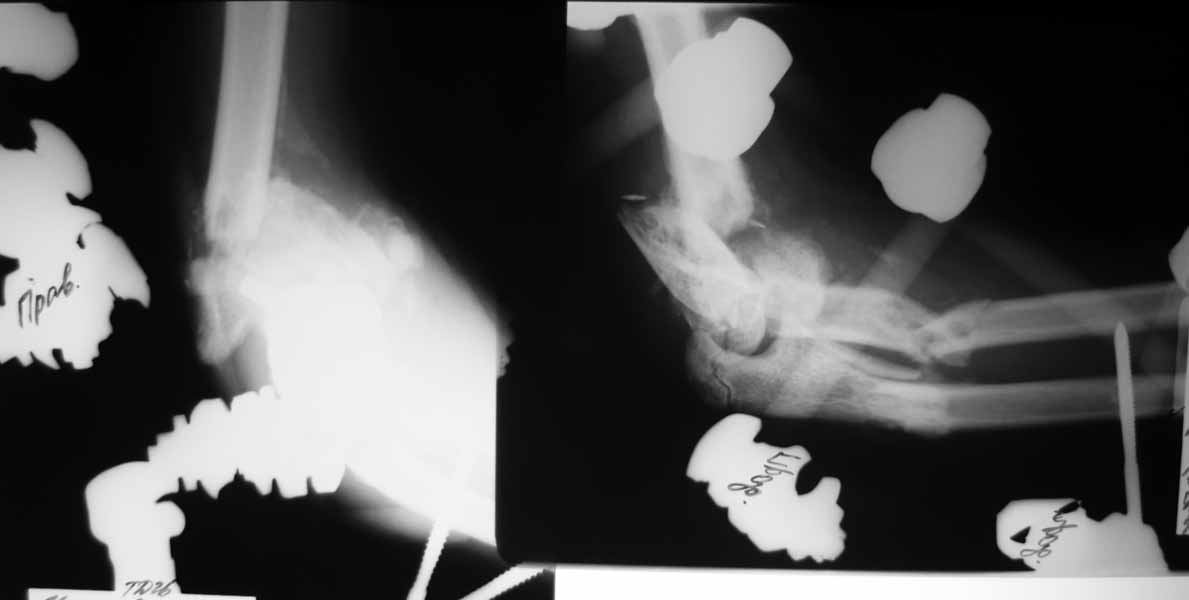

Насколько оправдано снятие аппарата? В АВФ удобнее мыть, перевязывать, не так ли? Штанги графитовые и больших наводок при рКТГ не дадут. Выкладываю свежие рентгенограммы.

Мысли такие: на завтра сделаем некрэктомию участков локального сухого некроза кожи на локтевом суставе. Заживляем-первязываем. Лучевую кость есть желание синтезировать закрыто ESIN под ЭОП. Локтевую кость - открыто, как в пункте 4. Скорее всего - БИОС. Пункт 4 не вызывает никаких возражений. Смущает фраза первого оперирующего: что все отломки "вбиты в мышцы как при разделке мясником и обмотаны фасциями". При таком взаимоотношении с мягкими тканями сложно расчитывать на изящный выход из ситуации.